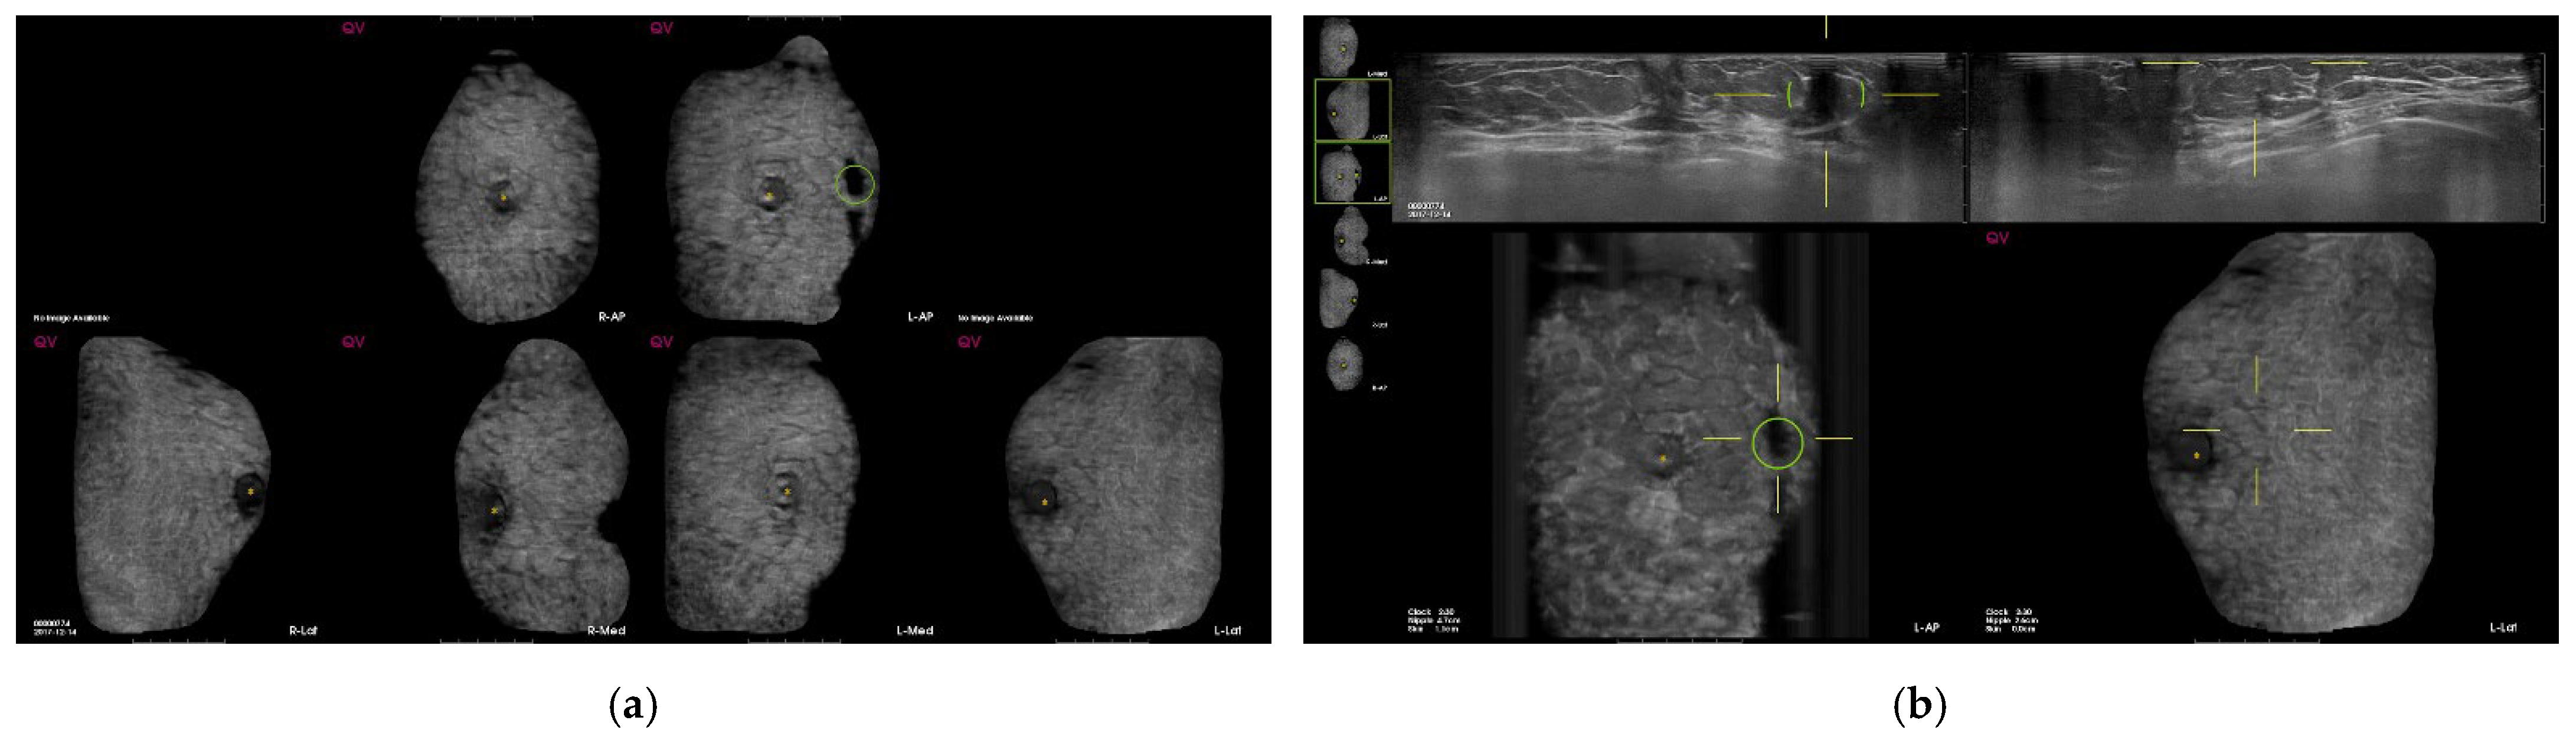

| Characteristics of All CAD Mark (n = 1032) | ||

| Mean and median No. of CAD marks per patient | ||

| mean ± SD | 0.8 ± 1 | |

| median (IQR) | 1 (0, 1) | |

| No. of CAD mark per patient | n | % |

| 0 (498) | 498 | 48.3 |

| 1 (1 × 223) | 223 | 21.6 |

| 2 (2 × 79) | 158 | 15.3 |

| 3 (3 × 36) | 108 | 10.5 |

| 4 (4 × 6) | 24 | 2.3 |

| 5 (5 × 3) | 15 | 1.5 |

| 6 (6 × 1) | 6 | 0.6 |